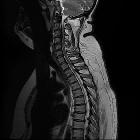

length, and enhancement: systematic approach to differentiating intramedullary spinal cord lesions. Compressive myelopathy. A 50-year-old patient with bilateral hand tingling. a Sagittal T2 image shows severe spinal canal narrowing at C3–C4 due to degenerative changes, with focal faint signal hyperintensity (arrow). b Post-contrast image shows focal enhancement (arrow)